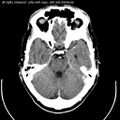

Computed tomography of head, with cerebellum visible at lower part